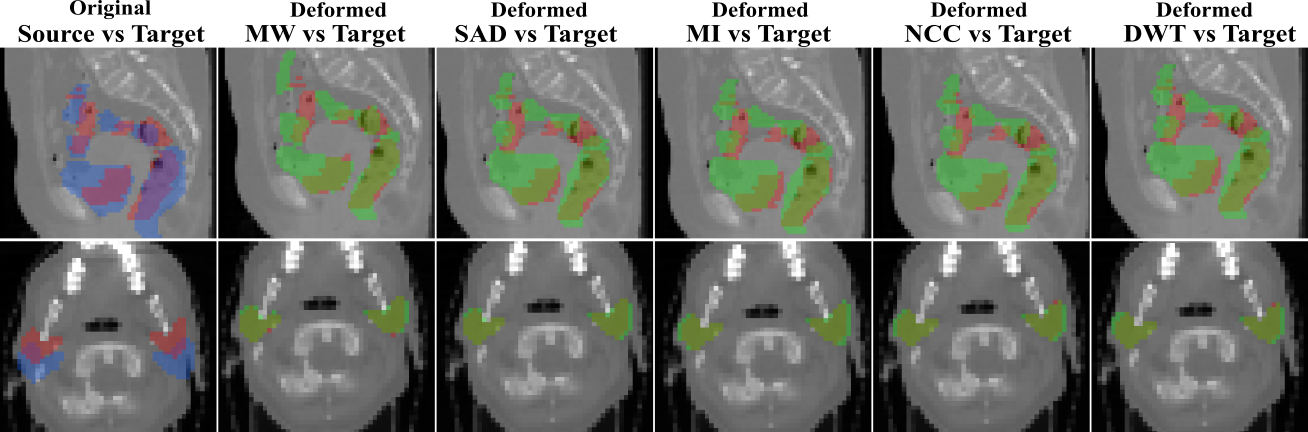

7 Qualitative results

Below we show visual results on three datasets used as a proof-of-concept for our proposed method, to highlight the effects of learning the weights of different metrics for the task of deformable registration.

Figure 4: Overlapping of the segmentation masks in different views for one registration case from RT Abdominal (first row) and RT Parotids (secibd row) datasets (views are different than those shown in the main paper). The first column corresponds to the overlapping before registration between the source (in blue) and target (in red) segmentation masks of the different anatomical structures of both datasets. From second to sixth column, we observe the overlapping between the warped source (in green) and the target (in red) segmentation masks, for the multiweight algorithm (MW) and for the single metric algorithm using sum of absolute differences (SAD), mutual information (MI), normalized cross correlation (NCC) and discrete wavelet transform (DWT) as similarity measure. We observe in a qualitative way that multiweight algorithm gives a better fit between the deformed and ground truth structures than the rest of the single similarity measures, which are over segmenting most of the structures showing a poorer registration performance. This is coherent with the numerical results reported in Figures 2 and 3 from the main paper.